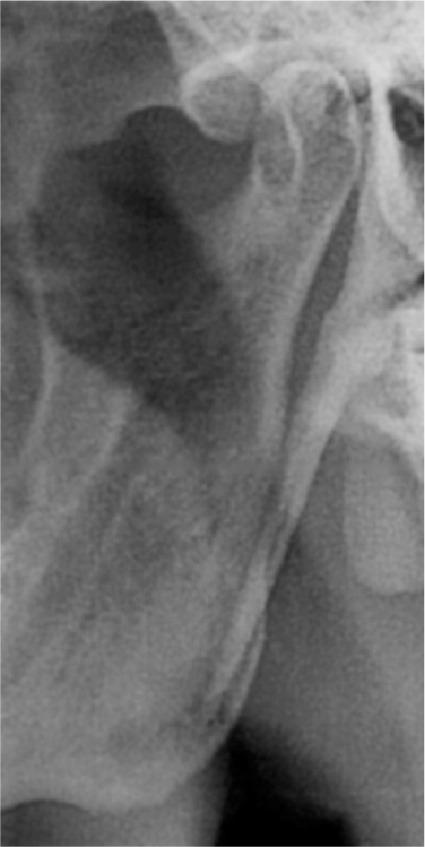

The objectives of this study were to assess the elongation of the styloid process on digital panoramic radiographs and to evaluate the prevalence of the elongation according to age, sex and types.

Digital panoramic radiographs of 198 geriatric edentulous patients were analyzed. The radiographic length of the styloid process was measured on both sides using the measurement toolbars on the accompanying analysis software. For statistical analysis, Student's -test, chi-square test and analysis of variance test were used.

The elongated styloid process was seen in 87 of the 198 patients. It was observed that as age increased, elongation of the styloid process increased with a male predominance. Type I elongation was more common than other types of elongation. Bilateral elongation was most commonly found than unilateral elongation, and both types of elongation were frequently seen in males compared with females.